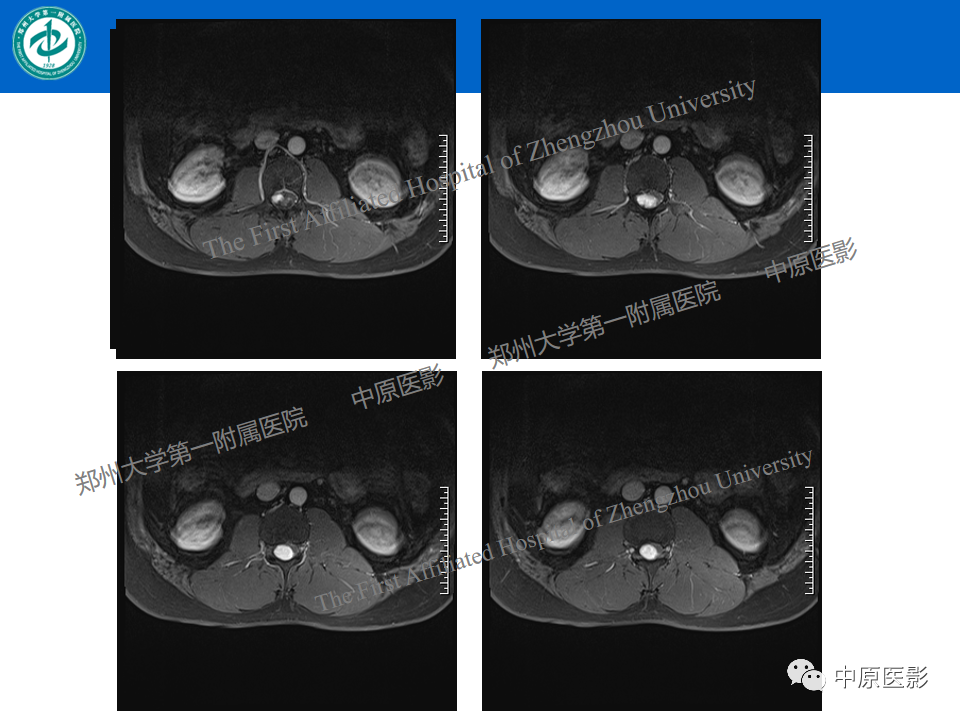

【病例】腰椎毛细血管瘤1例MR影像-1

【病例】腰椎毛细血管瘤1例MR影像-2

【病例】腰椎毛细血管瘤1例MR影像-3

【病例】腰椎毛细血管瘤1例MR影像-4